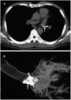

Bronchial foreign body

A bronchus is a passage or airway in the respiratory system that conducts air into the lungs. The first bronchi to branch from the trachea are the right main bronchus and the left main bronchus, also known as the primary bronchi. [Source: Wikipedia ]